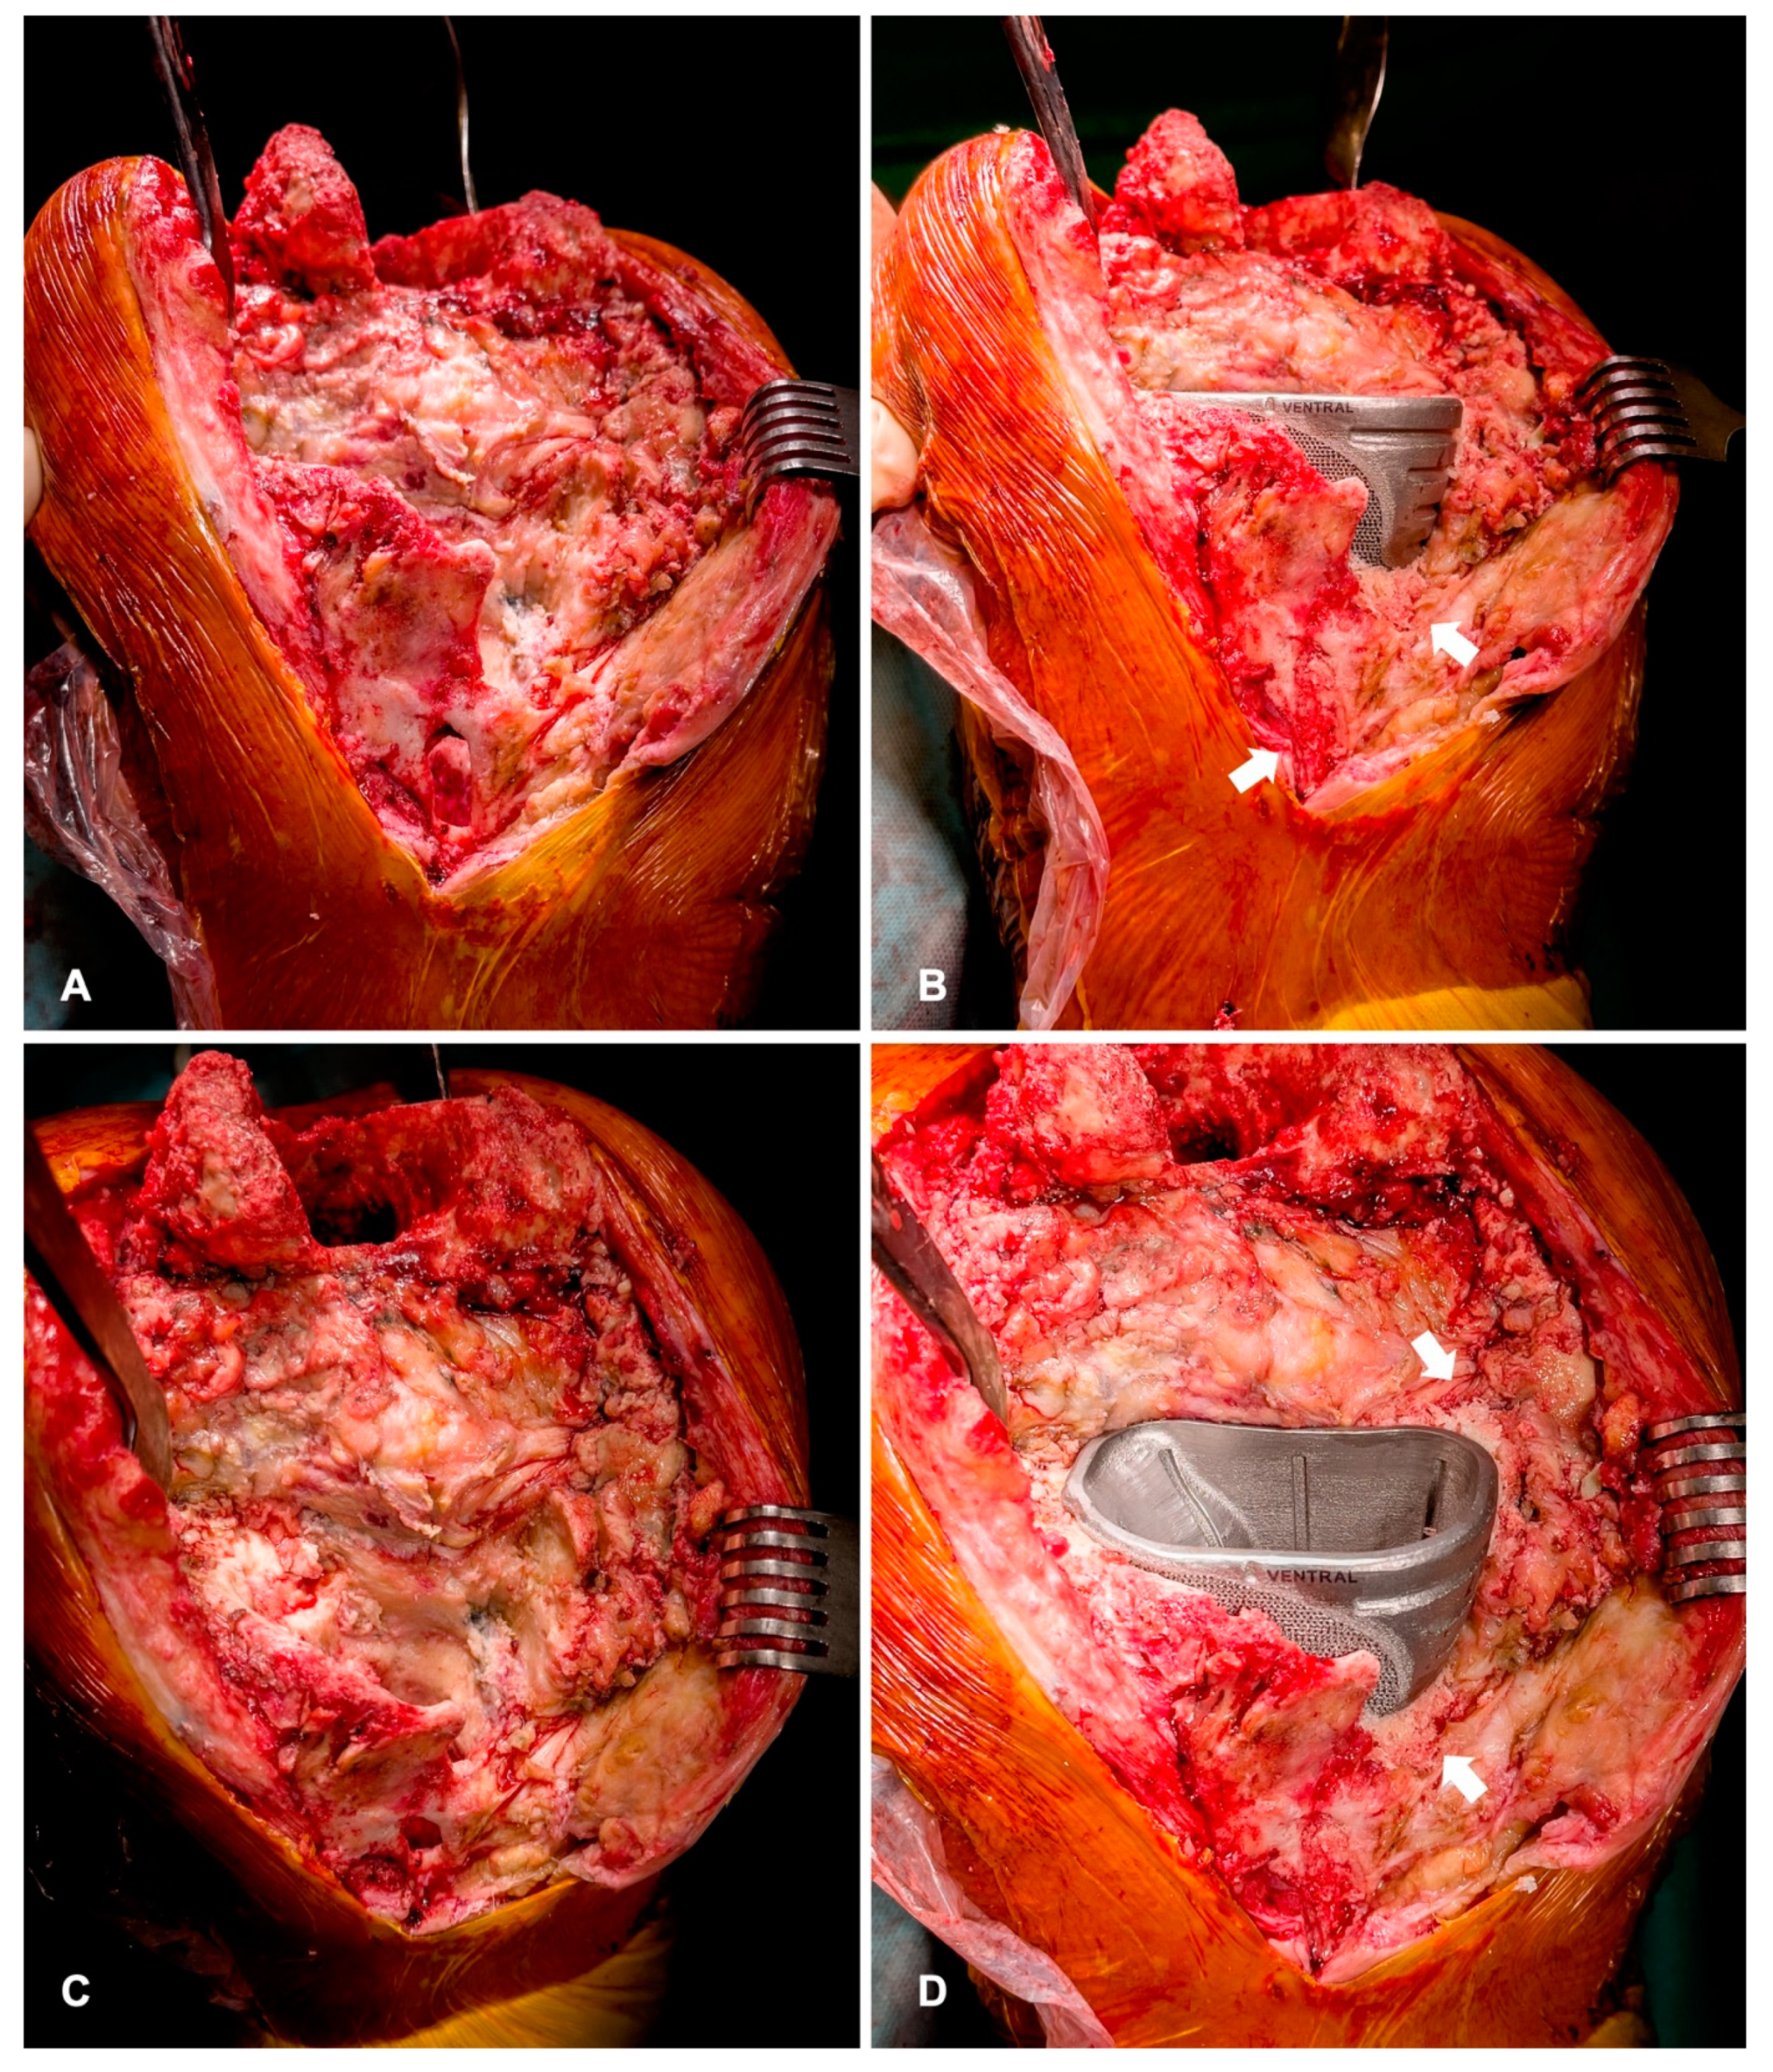

During the surgery, the bone bed is prepared with custom-made rasps, respectively, and impactors (Figure 6A,B). Trial implants can be used to check the position and progress of the preparation. The bone surface must be cleaned of any soft tissue such as pseudomembranes or cement residues to enable the best possible osteointegration to the cone surface. Bone-impaction grafting can be used to fill the remaining defects (Figure 7). The stems are usually cemented (Figure 1B).

Figure 7.

(A,C) Intraoperative findings of severe defect of the tibial metaphysis. The complete medial plateau is loss. (B,D) After cementless implantation of the cone, defects are filled with bone-impaction grafting (arrows). This leads to secondary osteointegration and partial reconstruction of the bone defect.